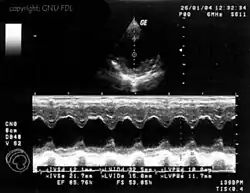

M-Mode

Eine weitere häufig eingesetzte Darstellungsform ist der M- oder TM-Mode (englisch für (time) motion). Dabei wird ein Strahl bei einer hohen Impulswiederholungsfrequenz (1 – 5 kHz) eingesetzt. Die Amplitude des Signals wird auf der vertikalen Achse dargestellt; die von den hintereinander liegenden Impulsen erzeugten Echozüge sind auf der horizontalen Achse gegeneinander verschoben. Diese Achse stellt also die Zeitachse dar.

Bewegungen des Gewebes bzw. der untersuchten Strukturen haben Unterschiede in den einzelnen Impulsechos zur Folge, es lassen sich Bewegungsabläufe von Organen eindimensional darstellen. Die M-Mode-Darstellung ist häufig mit dem B- bzw. 2D-Mode gekoppelt.

Ihre Hauptanwendung findet diese Untersuchungsmethode in der Echokardiografie, um Bewegungen einzelner Herzmuskelbereiche und der Herzklappen genauer untersuchen zu können. Die zeitliche Auflösung dieses Modus ist bestimmt durch die maximale Wiederholrate der Schallimpulse und beträgt schon bei 20 cm Tiefe über 3 kHz.